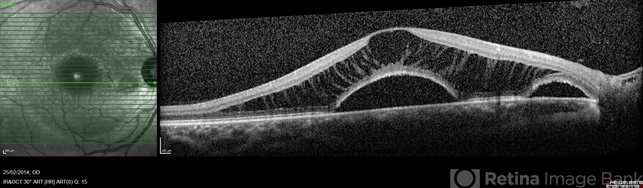

- optic disc pit, maculopathy, optical coherence tomography (OCT)

Optical coherence tomography system

Heidelberg Spectralis - Description

- Optic disc pit maculopathy of a 26-year-old man with optic disc pit maculopathy of his right eye.